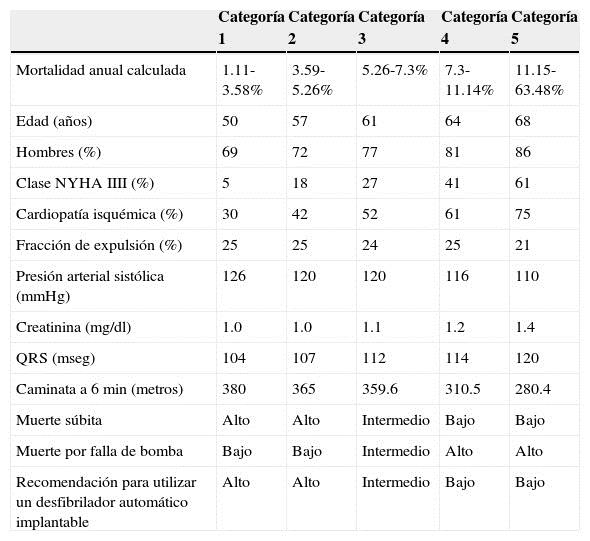

Los pacientes con insuficiencia cardiaca sistólica y fracción de expulsión persistentemente por debajo del 35% tienen alto riesgo de fallecer por muerte súbita o por progresión de la insuficiencia cardiaca45,46. Es importante reconocer a los pacientes con mayor riesgo de paro cardiaco súbito, ya que son los candidatos apropiados para recibir un DAI con lo que se reduce su mortalidad47. La fracción de expulsión como único predictor de paro cardiaco súbito tiene limitaciones y es insuficiente, por lo que es necesario utilizar otros marcadores48. Clasificar a los pacientes con insuficiencia cardiaca sistólica utilizando la escala de Seattle permite dividirlos en 5 categorías; las categorías con mayor riesgo de paro cardiaco súbito son las categorías 1 y 2, intermedio la categoría 3 y bajo las categorías 4 y 549. Las categorías 4 y 5 tienen mayor riesgo de fallecer por progresión de falla de bomba. Esta clasificación nos permite optimizar los recursos y tener una mejor recomendación para utilizar un DAI50 (Tabla 4). Los pacientes con insuficiencia cardiaca "diastólica" (fracción de expulsión preservada) tienen también una alta prevalencia de muerte súbita cardiaca51, por lo que es otro grupo que deberá ser clasificado para detectar a aquellos pacientes con alto riesgo de paro cardiaco súbito y puedan ser beneficiados con un DAI para reducir su mortalidad3. Los pacientes con insuficiencia renal son un grupo de alto riesgo de muerte súbita. Según el registro de datos renales de EE. UU. (US Renal Data System), el 22% de todas las muertes en estos pacientes son por muerte súbita cardiaca52. La incidencia se incrementa con la edad, un 2% por año para pacientes entre 20 y 44 años de edad, un 3.7% por año para pacientes entre 45 y 64 años de edad y un 7% por año para aquellos de 65 años o más53. Se ha determinado que el daño renal es un predictor independiente de paro cardiaco súbito y afecta tanto a hombres como a mujeres54.

Tabla 4 Escala de Seattle de insuficiencia cardiaca sistólica modificada y nivel de recomendación aproximado para la utilización de desfibrilador automático implantable

Modificada de Levy et al. 49.